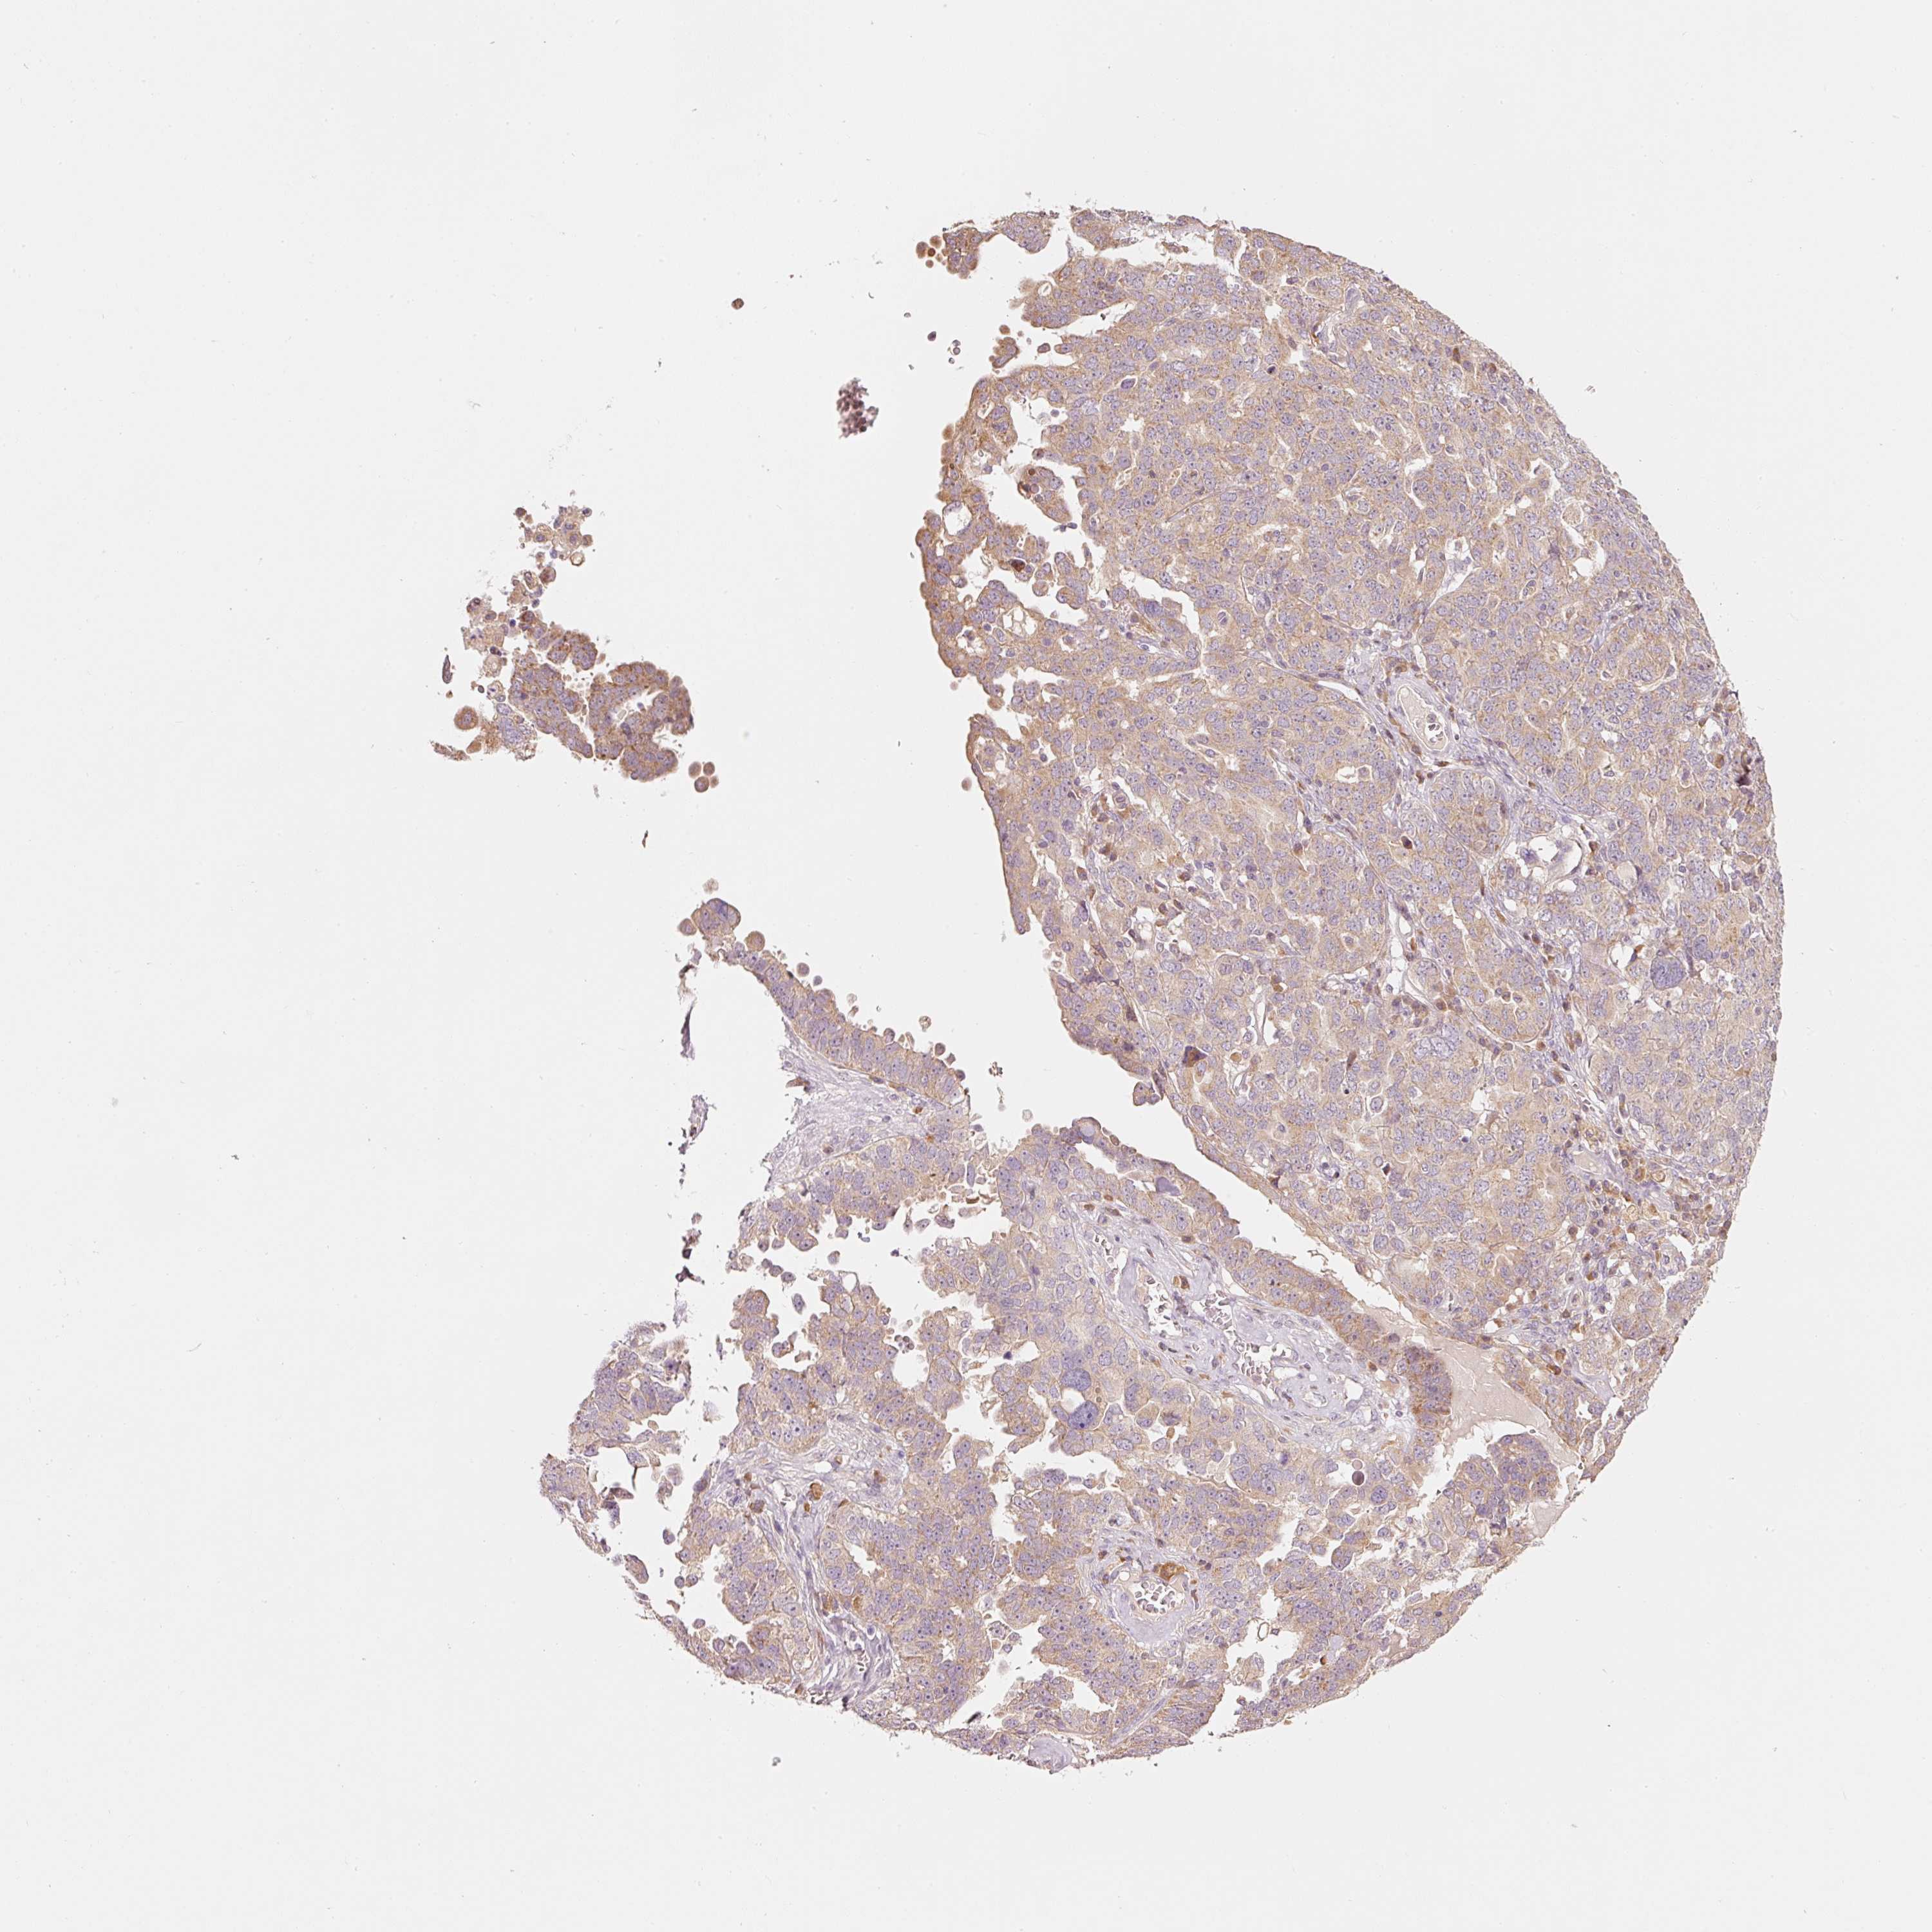

OVARIAN CANCER - Protein expressioni

A mouse-over function shows sample information and annotation data. Click on an image to view it in a full screen mode. Samples can be filtered based on level of antibody staining by selecting one or several of the following categories: high, medium, low and not detected. The assay and annotation is described here.

Note that samples used for immunohistochemistry by the Human Protein Atlas do not correspond to samples in the TCGA dataset.

Antibody stainingi

Antibody staining in the annotated cell types in the current human tissue is reported as not detected, low, medium, or high, based on conventional immunohistochemistry profiling in selected tissues. This score is based on the combination of the staining intensity and fraction of stained cells.

Each image is clickable and will lead to virtual microscopy that enables deeper exploration of all samples and also displays staining intensity scores, fraction scores and subcellular localization as well as patient and tissue information for each sample.

Antibody HPA052496

Staining

High

Medium

Low

Not detected

Intensity

Strong

Moderate

Weak

Negative

Quantity

>75%

75%-25%

<25%

None

Location

Nuclear

Cytoplasmic/membranous

Cytoplasmic/membranous,nuclear

Cystadenocarcinoma, serous, NOS

Carcinoma, endometroid

Cystadenocarcinoma, mucinous, NOS

Carcinoma, NOS